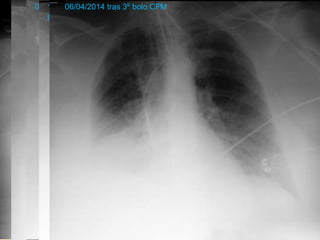

 Evolución PULMONAR:

◦ IOT (17/02/2014)

16/02/201425/02/2014 tras CC01/03/2014 1º bolo CFM10/03/2014 tras

plasmaféresis

19/03/2014 tras 2º bolo

CFM

06/04/2014 tras 3º bolo CFM

EVOLUCIÓN CLÍNICA PACIENTE Evolución PULMONAR: ◦ VMNI ◦ IOT (17/02/2014) ◦ Traqueostomía (19/03/2014) ◦ FBC  confirma hemorragia alveolar 16/02/201425/02/2014 tras CC01/03/2014 1º bolo CFM10/03/2014 tras plasmaféresis 19/03/2014 tras 2º bolo CFM 06/04/2014 tras 3º bolo CFM